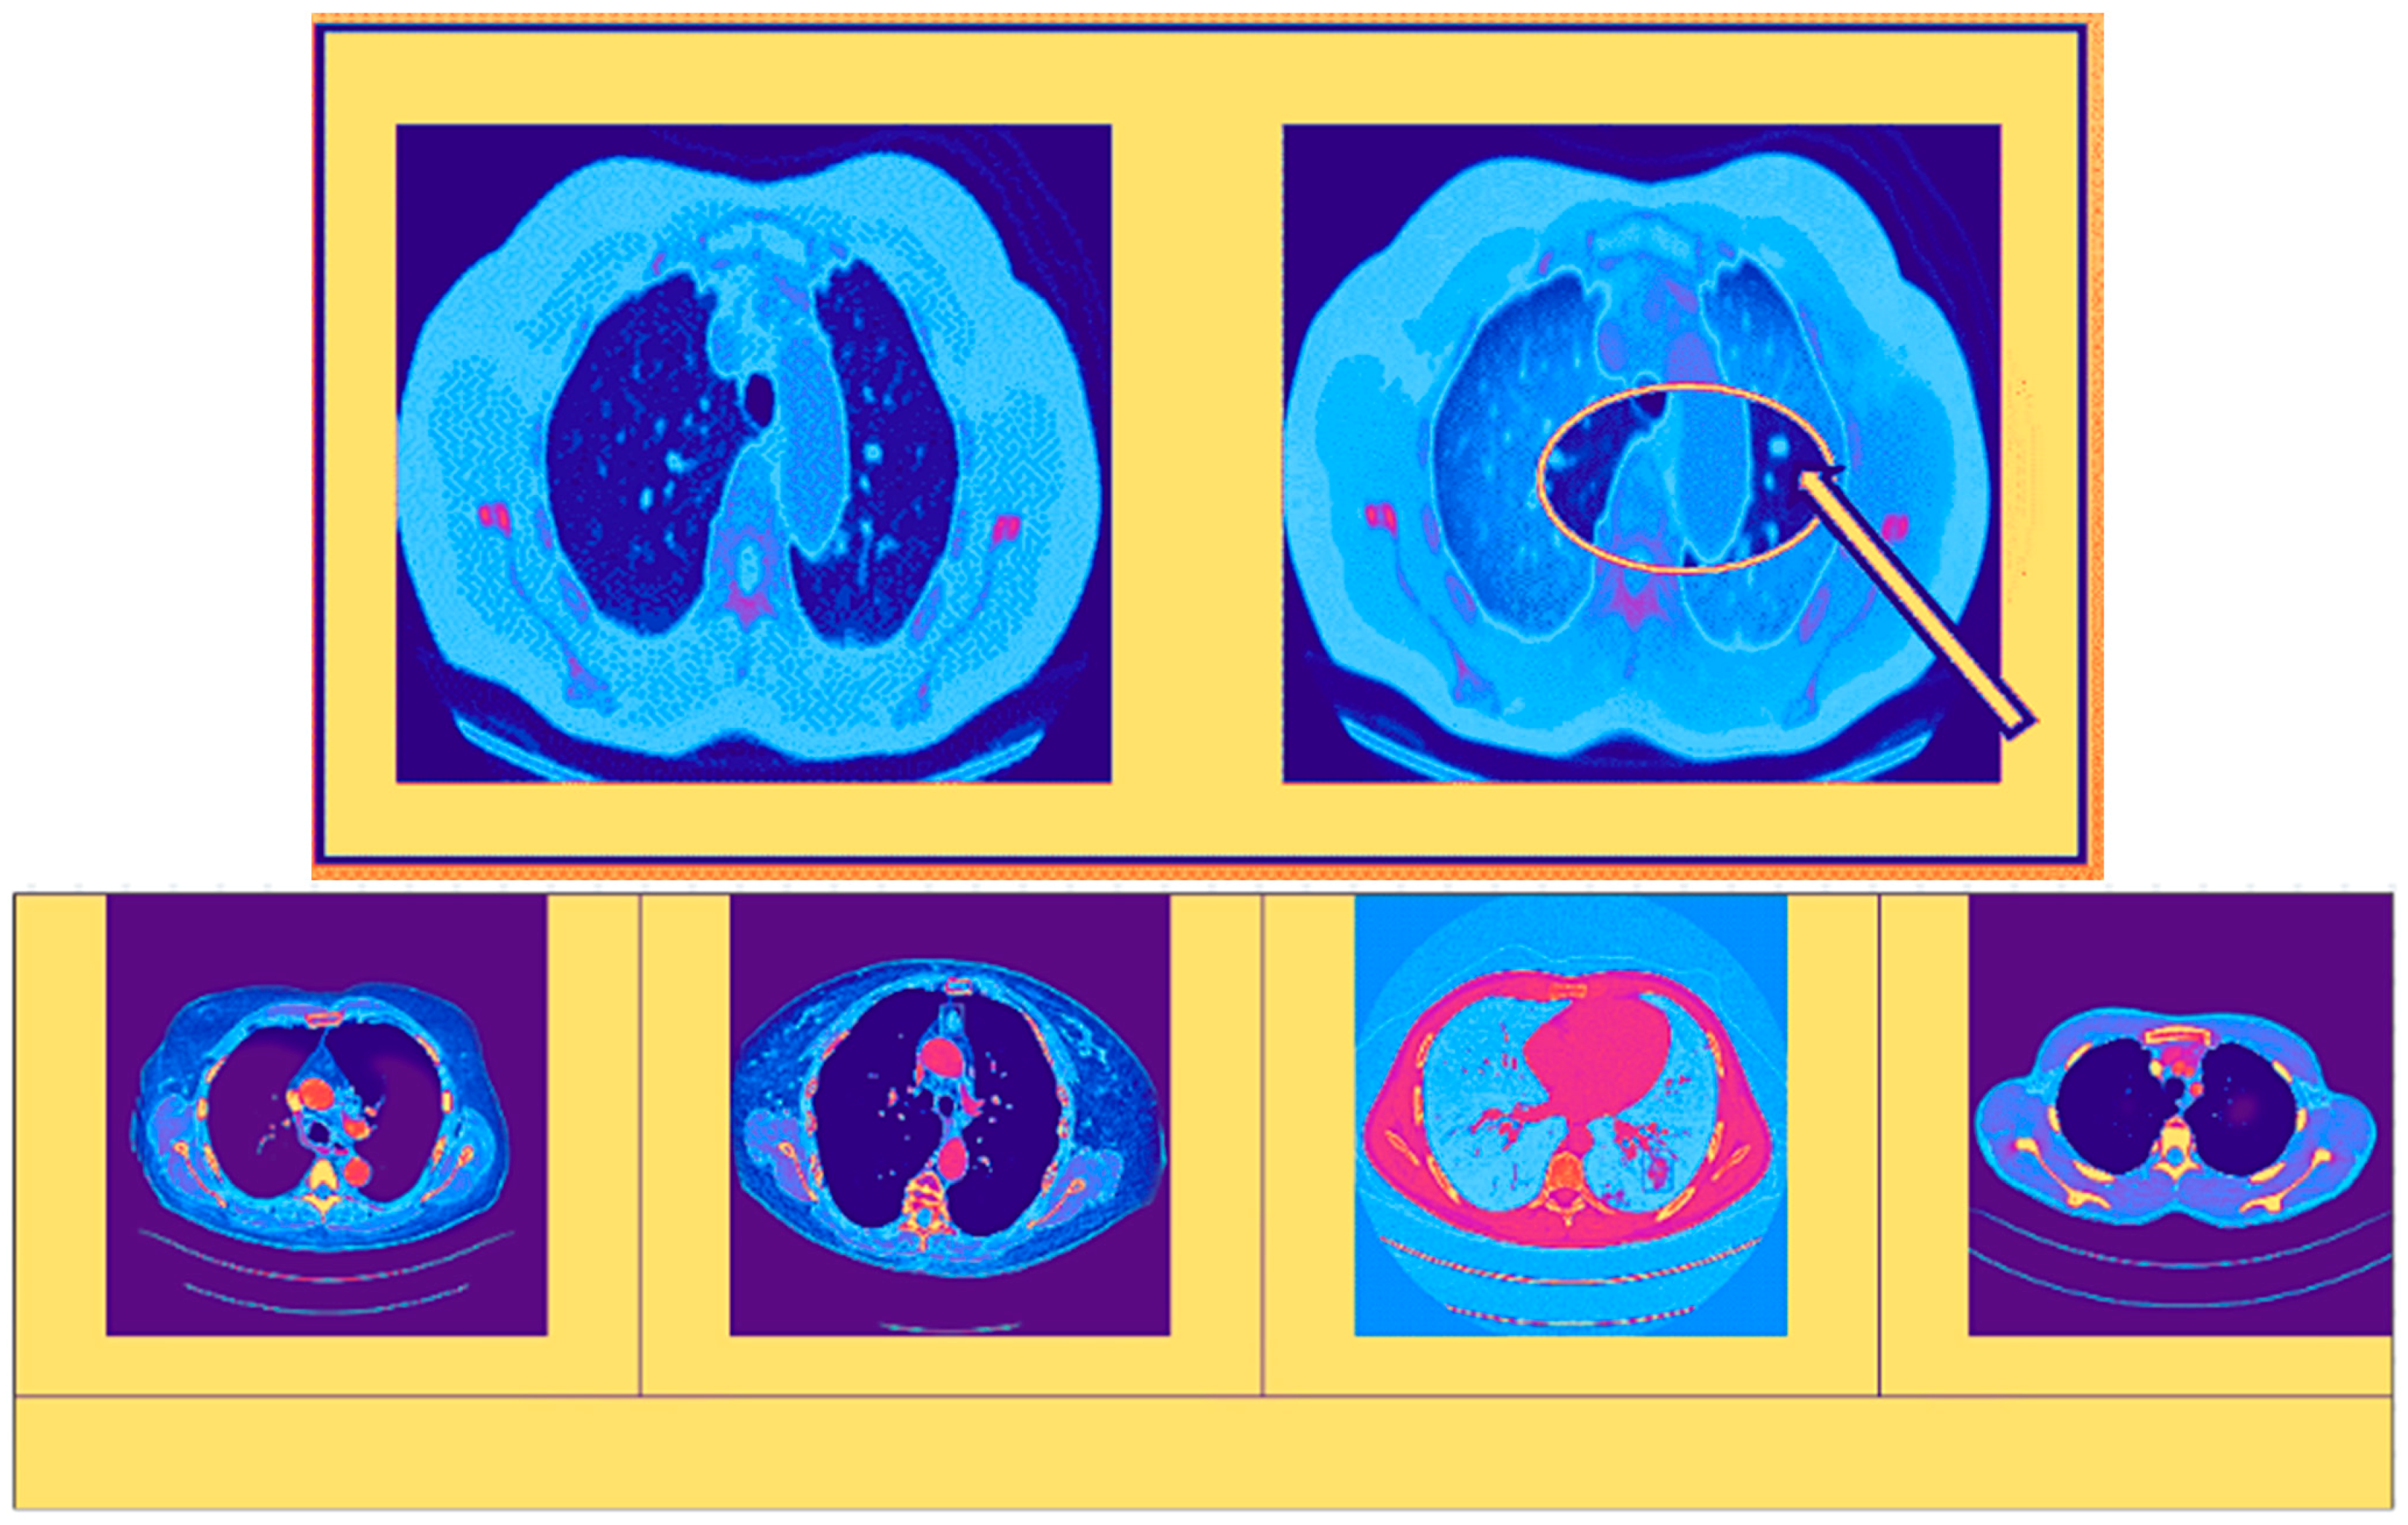

In the figure, the images help doctors make well-informed decisions and improve patient care strategies by providing a thorough awareness of the extent and distribution of malignant tumors through a visual contrast between normal cancerous images on the left side and enhanced cancerous diseased tissue images on the right side. The area that has been highlighted in Figure 5 (using arrow) is the cause for concern and requires additional investigation. Herein, we have used red color to indicate tumor. This might be a tumor, nodule, or another abnormality that has to be examined more closely to rule out malignancy or benignity.

Figure 5.

Left and right with cancer and highlighted cancerous image.